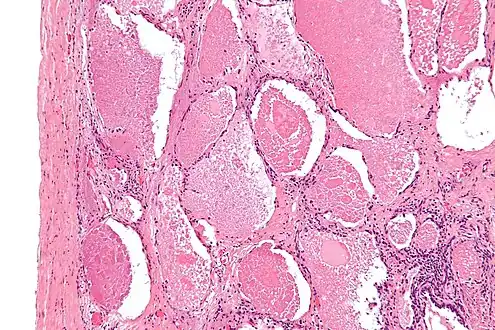

Intermediate magnification micrograph of pulmonary alveolar proteinosis. H&E stain.

Lung washings or tissue for histopathologic analysis are most commonly obtained using bronchoalveolar lavage and/or lung biopsy.[12] Characteristic biopsy findings show filling of the alveoli (and sometimes terminal bronchioles) with an amorphous eosinophilic material, which stains strongly positive on PAS stain and the PAS diastase stain. The surrounding alveoli and pulmonary interstitium remain relatively normal.[13] Electron microscopy of the sample, although not typically performed due to impracticality, shows lamellated bodies representing surfactant.[14] An alternative diagnosis with similar histomorphologic findings is Pneumocystis jirovicii pneumonia.[14]

Lung washings characteristically yield a fluid which is "milky"composition. Under the microscope, samples show 20-50 micrometer PAS-positive globules on a background of finely granular or amorphous PAS-positive material. There is typically a low numbers of macrophages and inflammatory cells (although this is variable).[13][14]